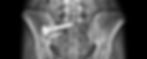

Perpendicular approach to the SIJ provides a safe pathway between the foramen, targets the body of S1 found to be the densest region of the sacrum to ensure optimal fixation, and allows for uniform decortication of the SI joint.

IDEAL TRAJECTORY

HIGHEST BONE DENSITY

(S1) BODY

A majority of systems utilize a lateral approach and attempt to anchor in low density bone.